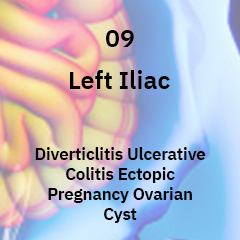

Ulcerative Colitis is a chronic inflammatory condition of the colon or the large intestine, which we encounter more frequently in our practice these days.